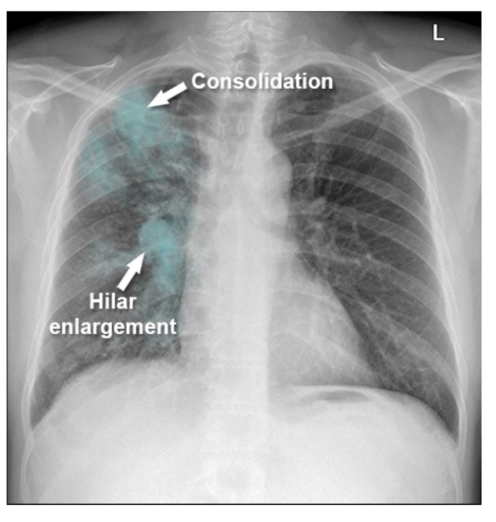

How does primary TB look on CXR?

image - can occur anywhere in lungs

• consolidations and hilar enlargement